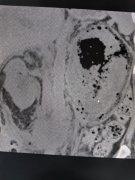

近日,莆田福德医院泌尿肾病科凭借精湛技术与高效协作,成功救治一名 移植肾输尿管结石引发急性肾衰竭的特殊肾移植患者 ,不仅挽回患者移植肾功能,更彰显科室在 复杂性泌尿系...